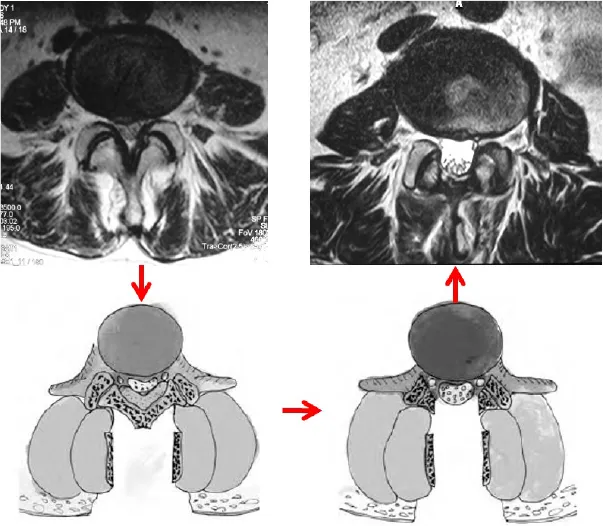

頚椎症性脊髄症

老化に伴い、脊髄の通り道(脊柱管)が狭くなり、脊髄が圧迫されると、さまざまな症状が生じます。頸部の痛み・四肢のしびれや痛み、進行すると細かい手の動きの障害・足のふらつきなどが出現します。

治療法:痛みやしびれだけであれば、内服薬によって症状は緩和しますが、運動障害があれば保存治療は無効です。手術は脊柱管を広げる方法(椎弓形成術)が一般的に行われます。手術の翌日から歩行が可能となり、入院期間は1〜2週間程度です。

頚椎症性脊髄症に対する椎弓形成術

-

術前MRI

術後MRI